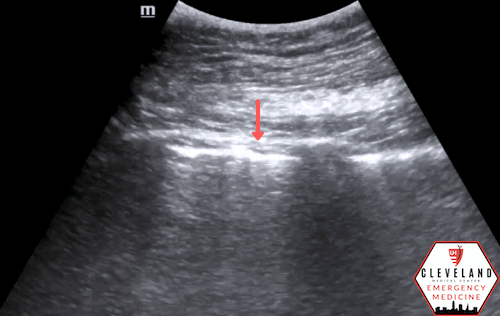

Subtle lung point - absent sliding (left) meets sliding (right)

Key Diagnostic Finding: The Lung Point

The lung point represents the interface between normally aerated lung and pneumothorax, with pleural sliding present on one side and absent on the other (10), see figure 5. The lung point has a reported sensitivity of approximately 66% and a specificity approaching 100% for pneumothorax (11).

M-mode can help confirm a lung point by demonstrating a transition from the barcode sign to the seashore sign as the pleural interface alternates between absent and normal sliding (figure 6).

Figure 5. Lung point